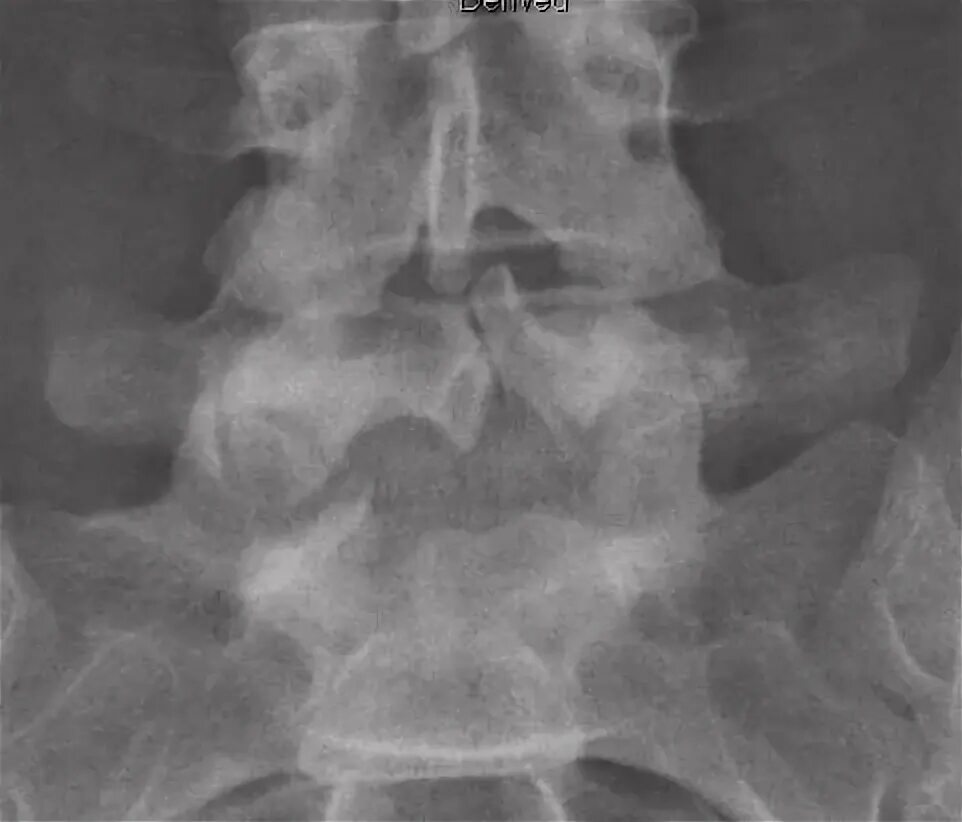

Незаращение дужки позвонка